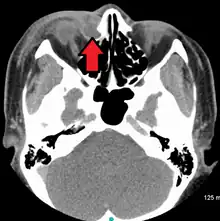

A case of dacryocystitis as seen on CT scan

Dacryocystitis is an infection of the lacrimal sac, secondary to obstruction of the nasolacrimal duct at the junction of lacrimal sac.[1] The term derives from the Greek dákryon (tear),[2] cysta (sac), and -itis (inflammation). It causes pain, redness, and swelling over the inner aspect of the lower eyelid and epiphora. When nasolacrimal duct obstruction is secondary to a congenital barrier it is referred to as dacryocystocele. It is most commonly caused by Staphylococcus aureus and Streptococcus pneumoniae.[3] The most common complication is corneal ulceration, frequently in association with S. pneumoniae.[3] The mainstays of treatment are oral antibiotics, warm compresses, and relief of nasolacrimal duct obstruction by dacryocystorhinostomy.[3]